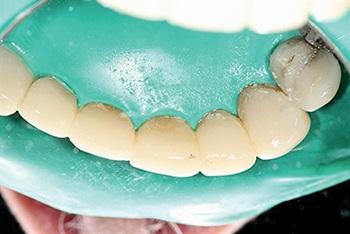

At presentation, the patient showed significant wear on the anterior teeth, with the lower incisors nearly absent from view and occlusion severely flattened (Fig. 1). The maxillary bicuspids sat buccal to their lower counterparts. The patient reported no pain, and radiographs showed no active pathology.

Fig. 1: Pre-op wear